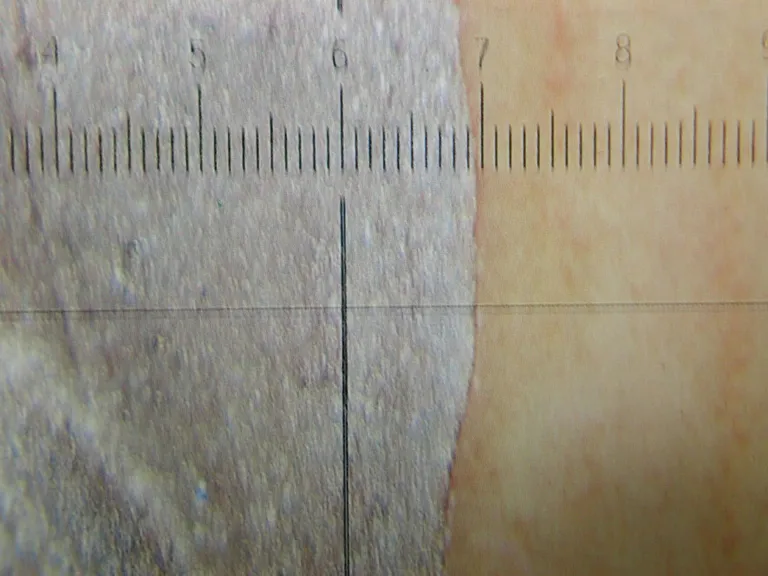

保険対応の治療が、目で見た範囲での技工である一方で、自費対応の治療では、技工士が20倍の実態顕微鏡で作業し、型どりした模型上で、縁の合わせ方が20ミクロン(50分の1ミリ)を目標にします。